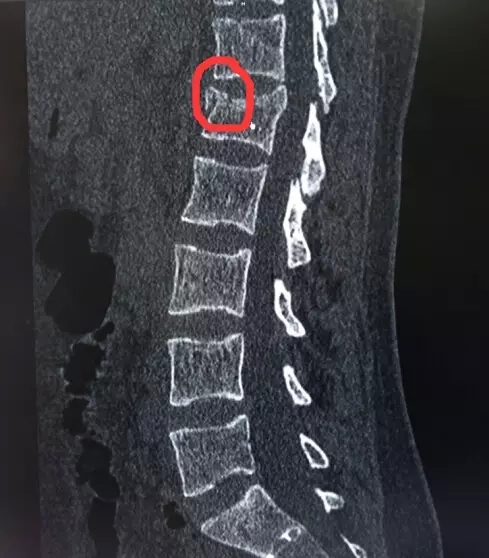

20

2015.03

胸腰椎骨折患者可到我院做微创手术